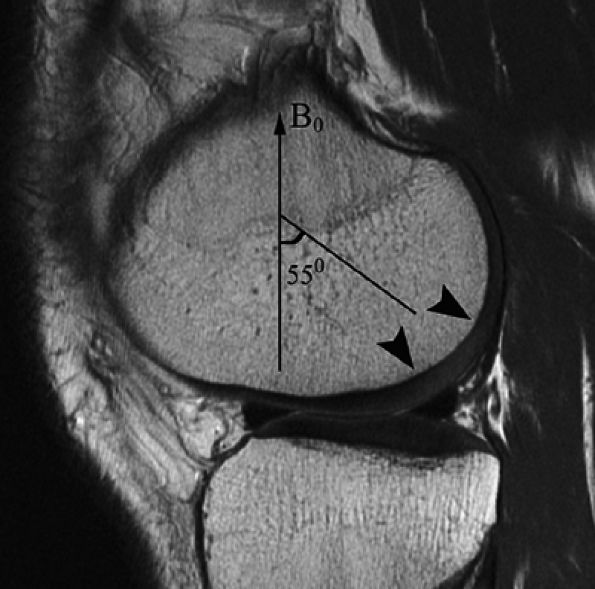

parallel to the long axis of the patient.80 When the angle between the external field and the hydrogen nuclei in collagen reaches approximately 55°, there is a corresponding prolongation of T2 relaxation time according to the relationship 1/T2 = k(3cos2&thetas; – 1). In the radial zone, where the collagen is highly ordered, expected prolongation of T2 has been noted in both high field strength microscopy systems at 7 Tesla as well as in images acquired on 1.5-Tesla units.80 Recognition of the magic angle effect in cartilage is important since it may produce apparent increased signal intensity in the radial zone at 55° (Fig. 7.12). Since the magic angle effect may hamper the measurement of cartilage regions of interest, caution should be used to avoid sampling T2 values at the magic angle.

FIGURE 7.12 ● A sagittal fast spin-echo MR image of the knee in a 26-year-old man demonstrates the magic angle effect (arrowheads), causing prolongation of T2 with focal loss of gray-scale stratification at 55° relative to the external magnetic field (B0), indicating highly ordered structure components in the cartilage matrix. Note the normal gray-scale stratification of the remaining medial femoral condyle and tibial plateau.